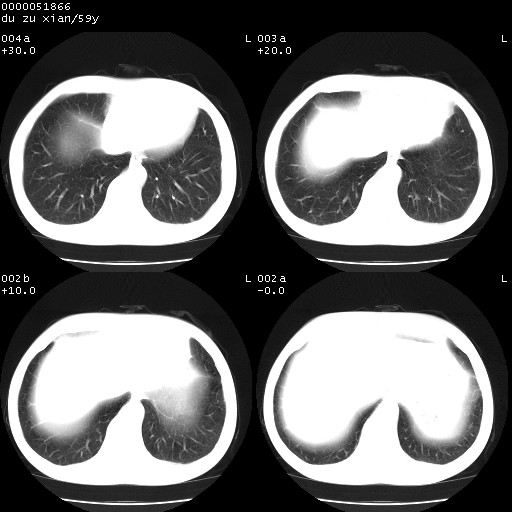

以下是引用宇宙ct在2008-8-25 23:21:00的发言:[br]右肺周围性肺癌并肋骨转移,纵隔淋巴结转移。

以下是引用zsl6918在2008-8-25 22:40:00的发言:[br]右肺周围性肺癌并肋骨转移,纵隔淋巴结转移。

以下是引用zy_zj在2008-8-26 15:24:00的发言:[br]单从病变本身,我倾向良性炎性病变,但肋骨转移了,所以说是考虑右肺周围性肺癌并肋骨、纵隔淋巴结转移可能性大。